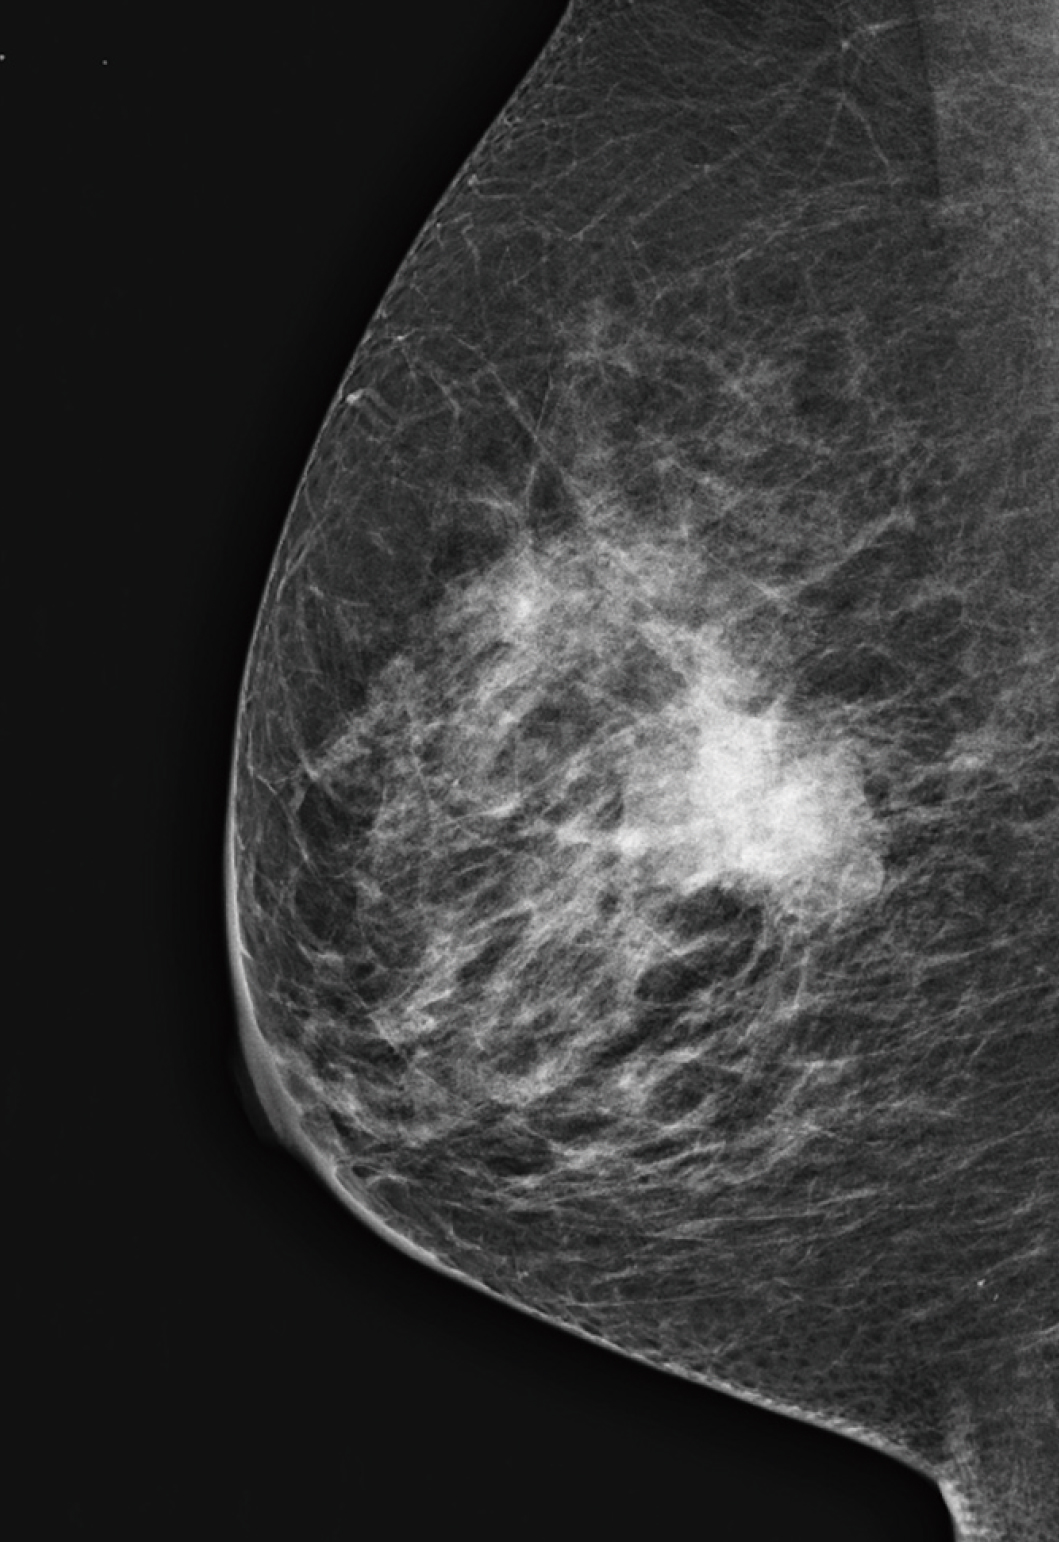

A tecnologia Image-based Spectrum Conversion*1 (ISC) pode ser usada para ajustar o contraste em uma imagem. A ISC analisa imagens para compensar variações no contraste devido à densidade das glândulas mamárias, à quantidade de gordura e ao espectro de raios X. A ISC visa garantir que as imagens exibam contraste adequado mesmo com o uso de um feixe de raios X de baixa dose e alta energia. Essa tecnologia permite que locais que anteriormente exploravam o contraste superior de um alvo de molibdênio percebam as vantagens de dose oferecidas pelo uso de tungstênio sem a necessidade de comprometer o contraste da imagem.

O Dynamic Visualization II (DYN II) exibe a densidade consistente e apropriada dos tecidos glandular e adiposo em cada tipo de mama, melhorando o contraste em mamas espessas e mamas densas. Além disso, ele fornece alto contraste sem saturação na região da mama, de modo que os locais possam definir o parâmetro de alto contraste.